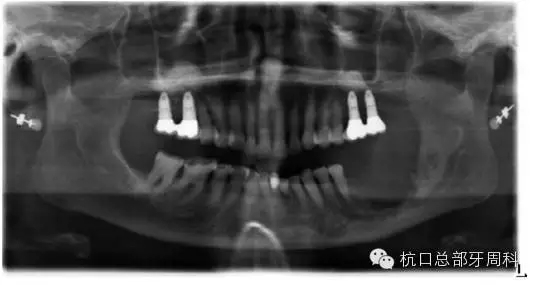

種植后即刻拍片  2005

110.webp.jpg